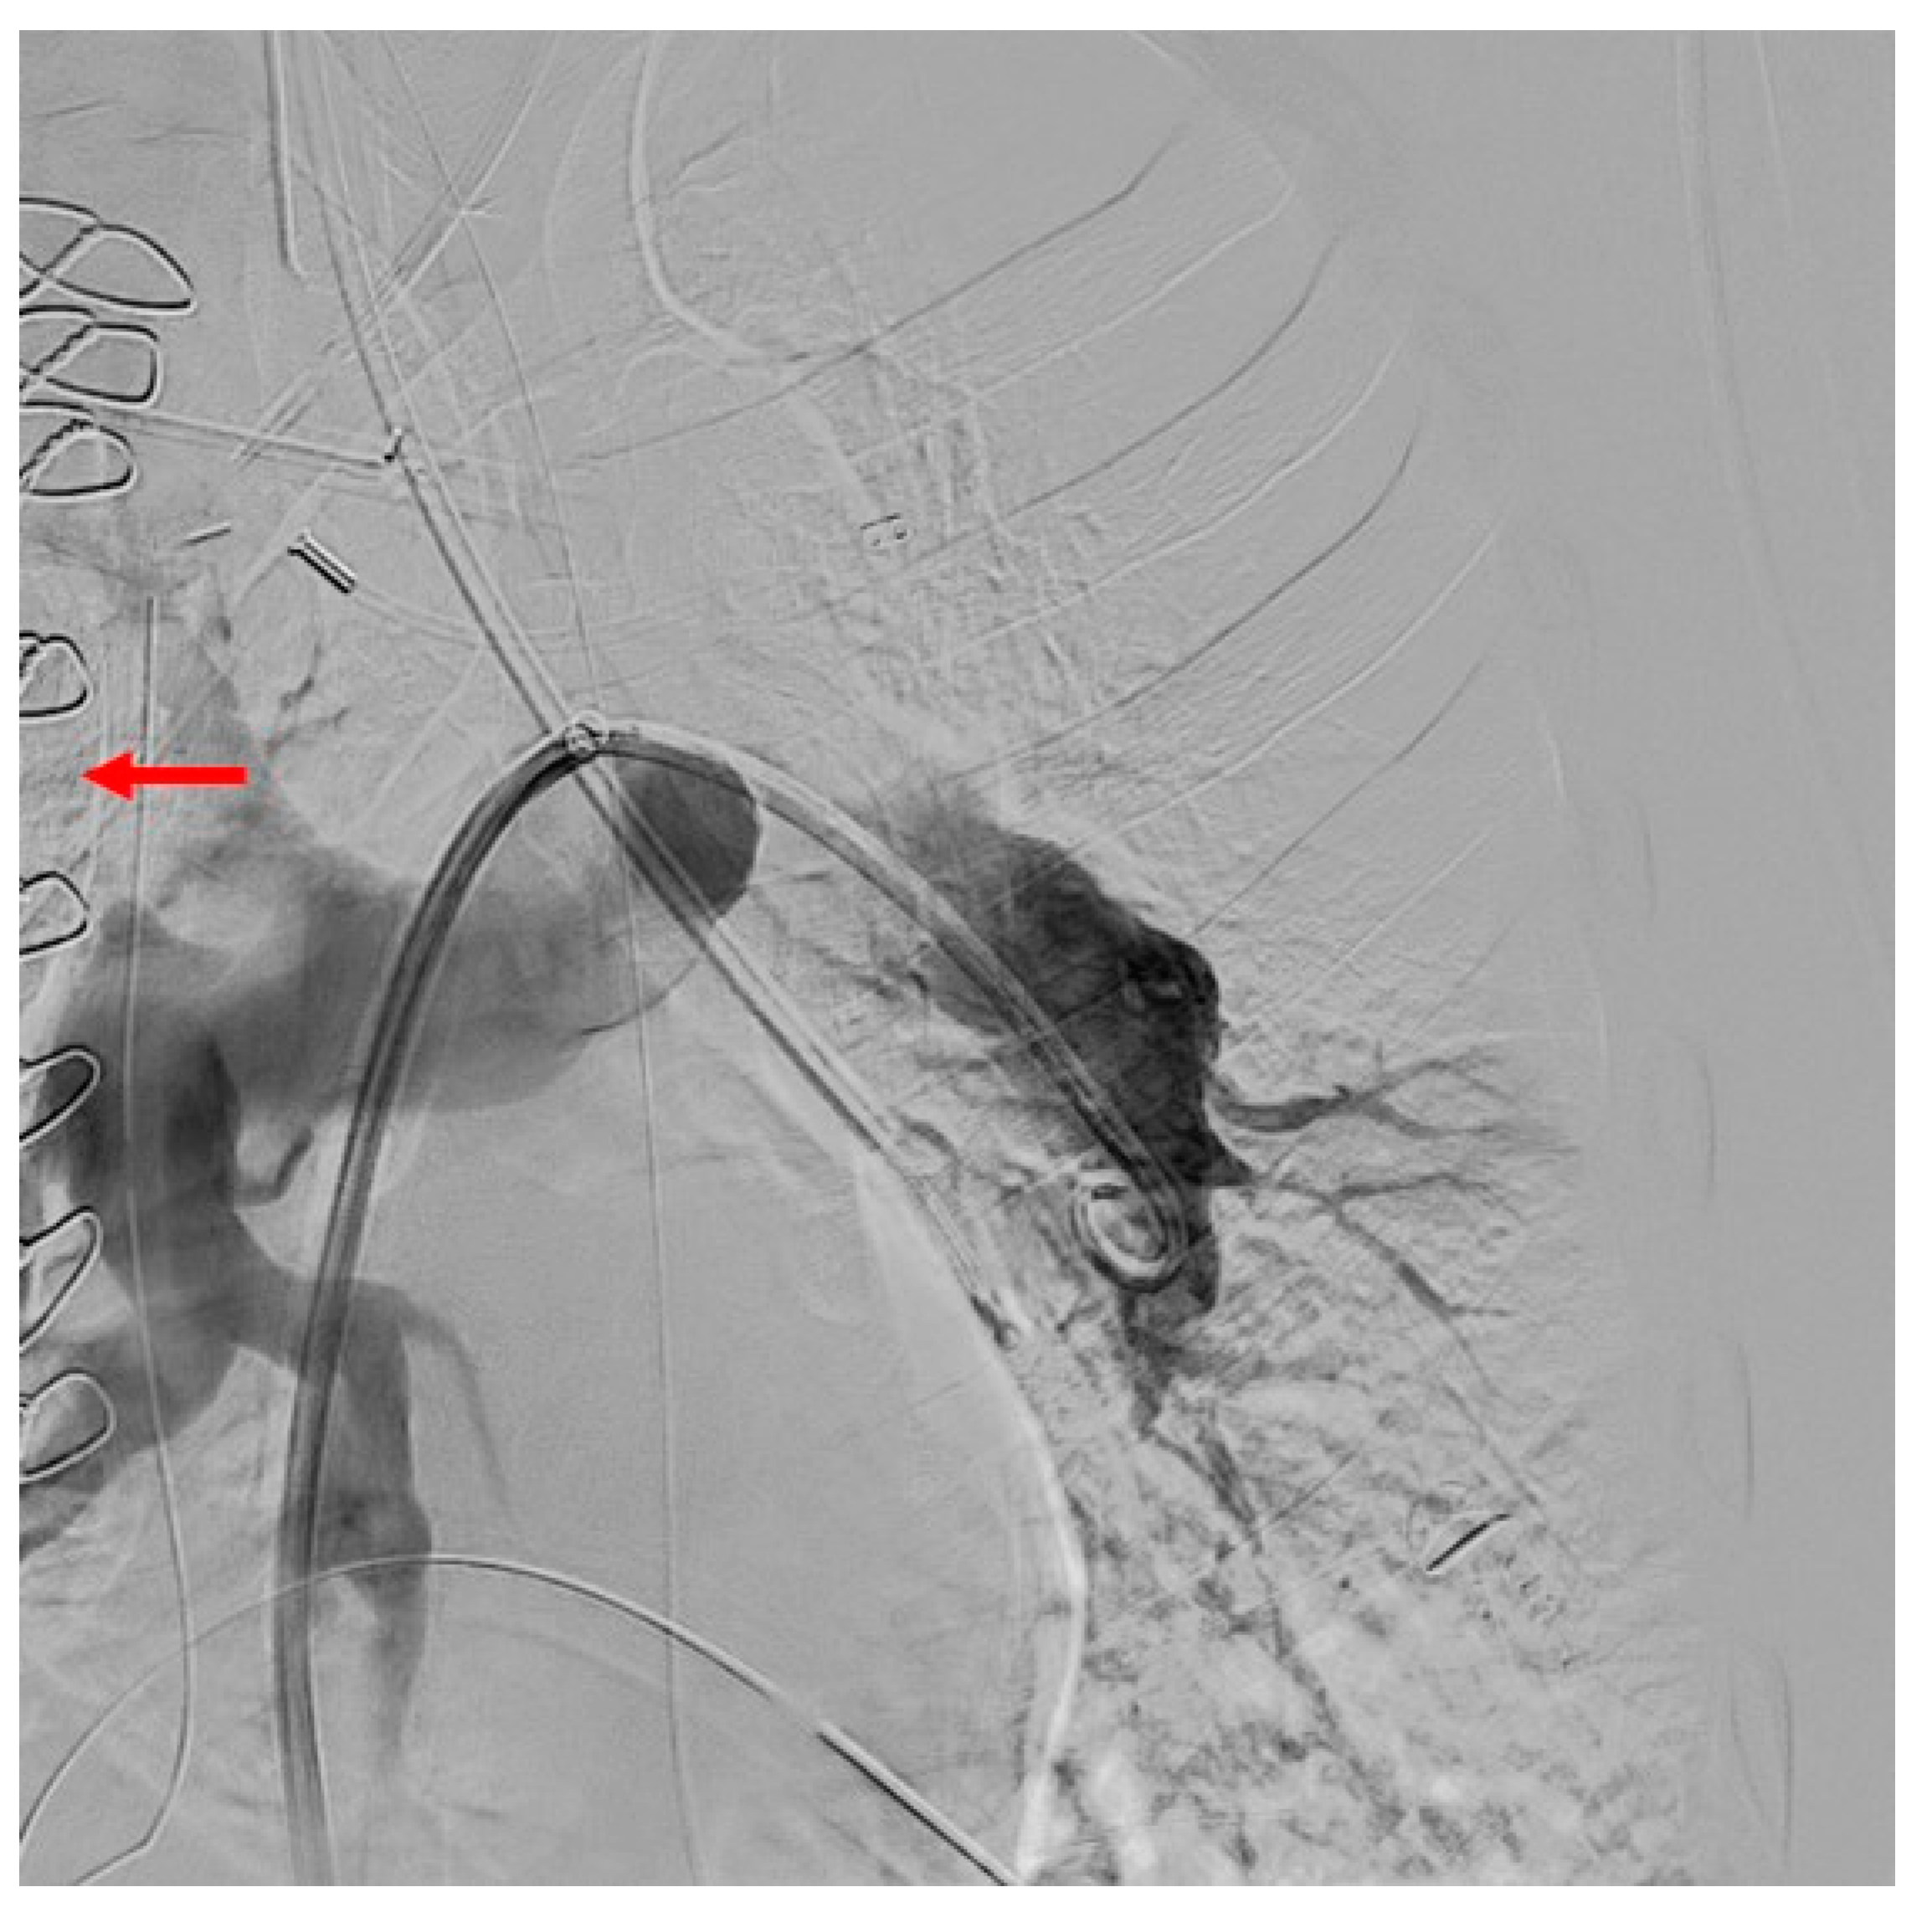

3.3. Imaging

3.4. Computed Tomography Pulmonary Angiography (CTPA)